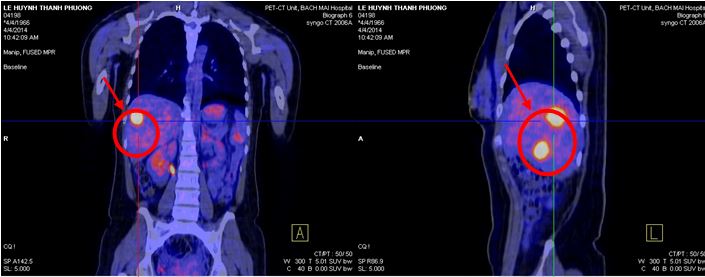

Bệnh nhân được chụp PET/CT đánh giá, (ngày 9/11/14) kết quả cho thấy: Gan: Hạ phân thùy VI có vùng tăng tỷ trọng trên hình ảnh cắt lớp vi tính nhưng không tăng hấp thu F-18 FDG, kích thước 1,8x 2,1cm. Ngoài ra không thấy bất thường khác.

Hình 4,5,6: Kết quả PET/CT sau điều trị (vòng tròn đỏ chỉ tổn thương): khối tổn thương di căn tại gan trái đã thu nhỏ kích thước hơn trước